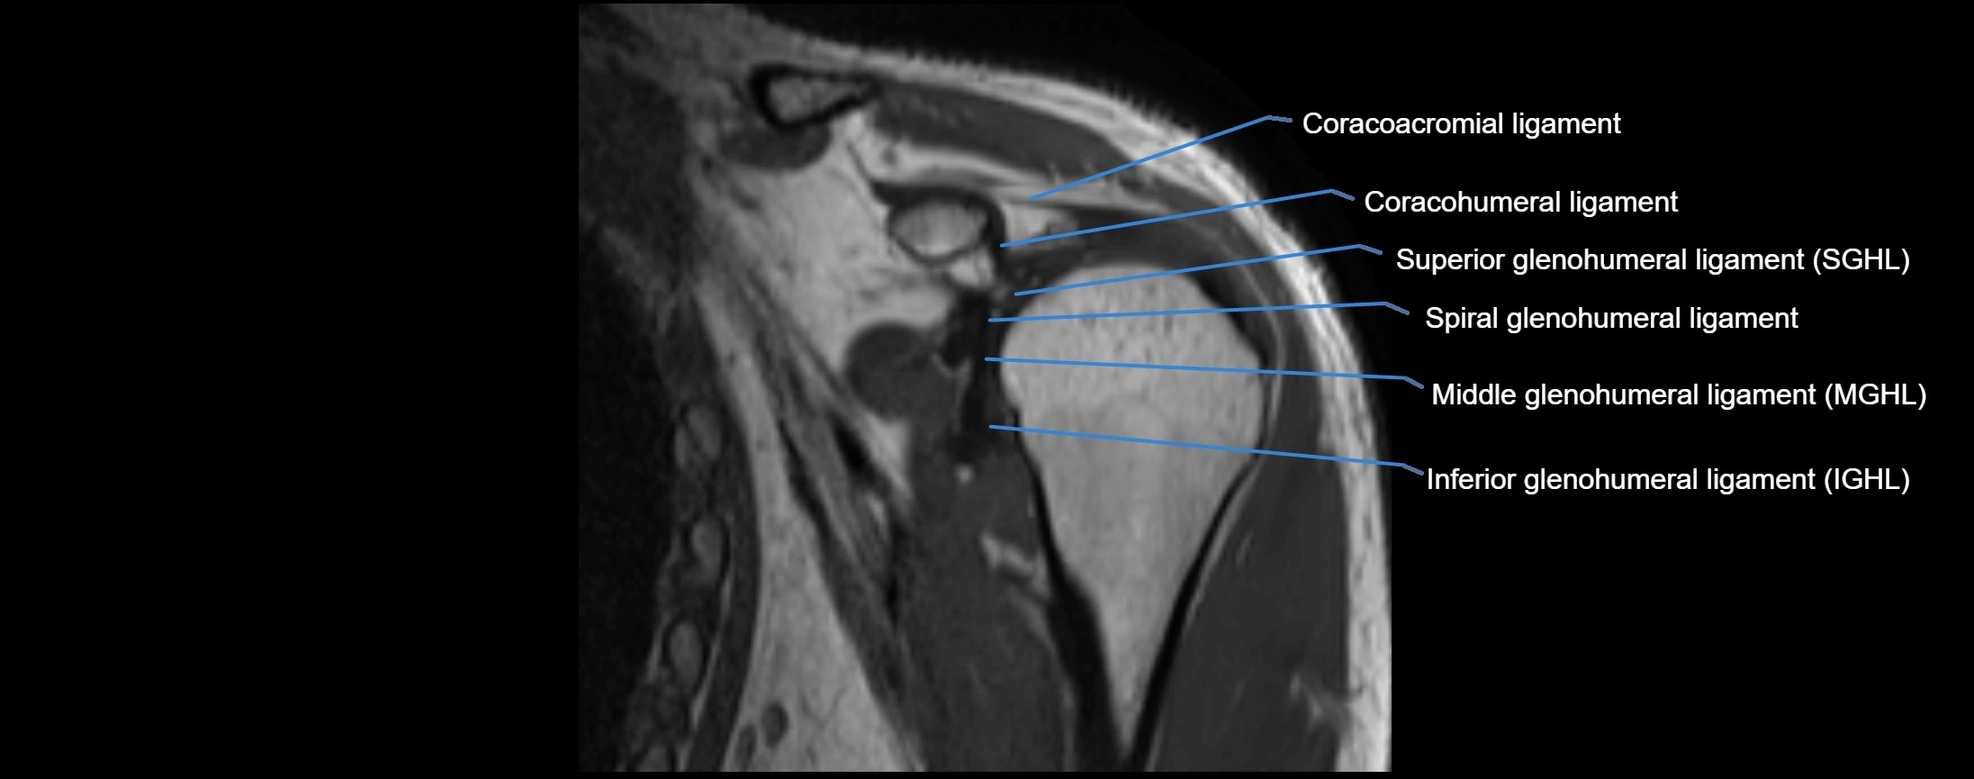

MRI images

image

MRI Appearance

• T1-weighted images:

• Normal ligament: Low signal (dark linear band) spanning acromion to clavicle.

• Surrounding fat planes: Bright, delineating the ligament clearly.

• Marrow of clavicle and acromion: Bright due to fatty content.

• Tears: Discontinuity or irregular thickening with intermediate-to-bright signal.

• Chronic injury: Thinning, fraying, or irregular low-signal fibers with adjacent scarring.

• T2-weighted images:

• Normal ligament: Low signal, homogeneous.

• Partial tear or sprain: Focal hyperintensity or thickening.

• Complete tear: Discontinuity with fluid-bright gap between clavicle and acromion.

• Associated edema: Bright signal in distal clavicle or acromion marrow.